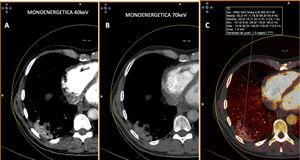

En cambio, en los pacientes que no mostraban TEP, cuando la enfermedad era extensa con múltiples lesiones pulmonares, se apreciaban zonas parcheadas de menor captación en las imágenes PBV (Pulmonary Blood Volume o mapa de perfusión pulmonar obtenido con energía dual). Posicionando una ROI (region of interest) en estas zonas, el realce de contraste era menor que en las zonas de pulmón sano. Construyendo mapas de color con dinteles de densidad más estrechos existían áreas de hipoperfusión pulmonar (fig. 7)48. Sin embargo, cuando las lesiones eran menores o la enfermedad más leve, no se observaban defectos de perfusión (fig. 8A) y las reconstrucciones e imágenes monoenergéticas de baja energía (40 KeV) permitían ver la permeabilidad de los vasos más distales. Además, las lesiones en vidrio deslustrado y sobre todo las consolidaciones podían captar contraste, lo que apoyaría, cuando la enfermedad es menos extensa y probablemente también en las fases iniciales, un origen inflamatorio (fig. 9). De forma similar, estudios de medicina nuclear realizados mediante 18FDG PET/TC muestran también un aumento de la actividad metabólica en las lesiones pulmonares, confirmando el componente inflamatorio como causa más probable de la afectación pulmonar (fig. 10)49. Como en muchos signos de esta enfermedad, no existe una clara explicación para estos hallazgos. Sin embargo, es planteable la hipótesis de que la infección vírica pulmonar en fases iniciales tiene un comportamiento inflamatorio; de hecho, en muchos casos se comporta, radiológicamente, como una neumonía organizativa criptogenética50, lo que explicaría la captación de las lesiones en las pruebas de imagen y resolución con tratamiento antiinflamatorio.

Paciente con COVID-19. Tomografía computarizada de doble energía. A y B) Imágenes monoenergéticas que muestran captación de la consolidación posterior y basal derecha, más evidente en la imagen monoenergética de baja energía (40 KeV). C) Imagen de mapa de yodo donde se aprecia captación de la lesión con aumento de densidad de 47 UH.